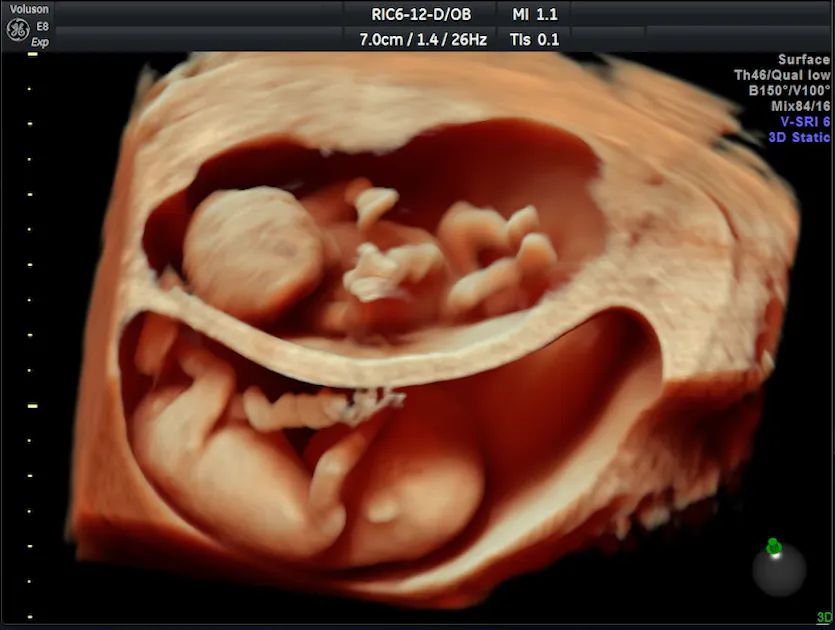

3D/4D Ultrasounds - Mother Nurture Ultrasound

www.mothernurtureultrasound.comultrasound 4d 3d hd 2d ultrasounds baby types animated gender technology mother packages gif imaging live difference clearview nurture check

www.mothernurtureultrasound.comultrasound 4d 3d hd 2d ultrasounds baby types animated gender technology mother packages gif imaging live difference clearview nurture check

Prenatal Ultrasounds | In Office 3D And 4D Ultrasounds!

mcwhc.comprenatal ultrasounds

mcwhc.comprenatal ultrasounds